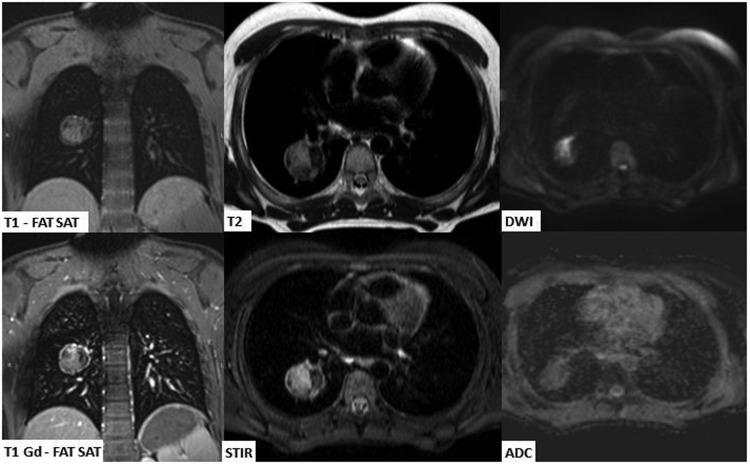

The purpose of this current pictorial review is to define the solitary round pulmonary lesion (SRPL), to familiarize with its prevalence in the pediatric population, and, moreover, to educate radiologists on its vast differential diagnosis and imaging manifestations. Furthermore, by highlighting valuable clues, it intends to assist radiologists efficiently partake in its diagnosis, work-up, and follow-up in order to narrow down the differential diagnosis by working alongside the clinician and combining clinical information, lab results, and radiological findings.

本次影像综述的目的是明确孤立性圆形肺病变(SRPL),使其在儿科人群中的患病率,此外,使放射科医生熟悉其广泛的鉴别诊断和影像学表现。此外,通过强调有价值的线索,旨在帮助放射科医生有效地参与其诊断、检查和随访,以便通过与临床医生合作并结合临床信息、实验室结果和影像学发现来缩小鉴别诊断范围。